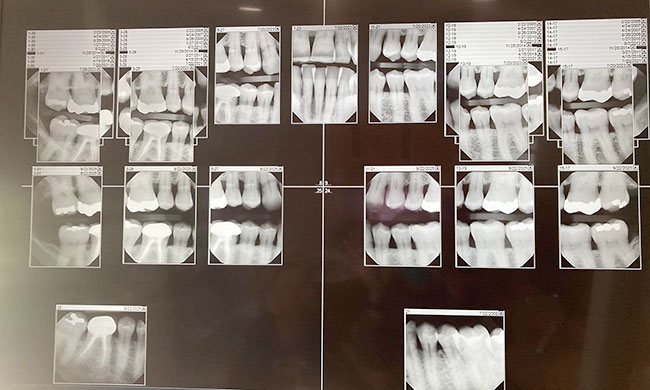

All this explains why I may be one of the few individuals who actually enjoys visits to the dentist. I am not put off by the roar of a drill, the scrape of a dental scaler, or the pinch of biting down on X-rays. Moreover, I absolutely love getting my teeth cleaned! I leave the dental office resolved to preserve my pristine palate and abstain from food and drink the rest of the day. Alas, within a few hours, my growling stomach inevitably triumphs over fresh breath.